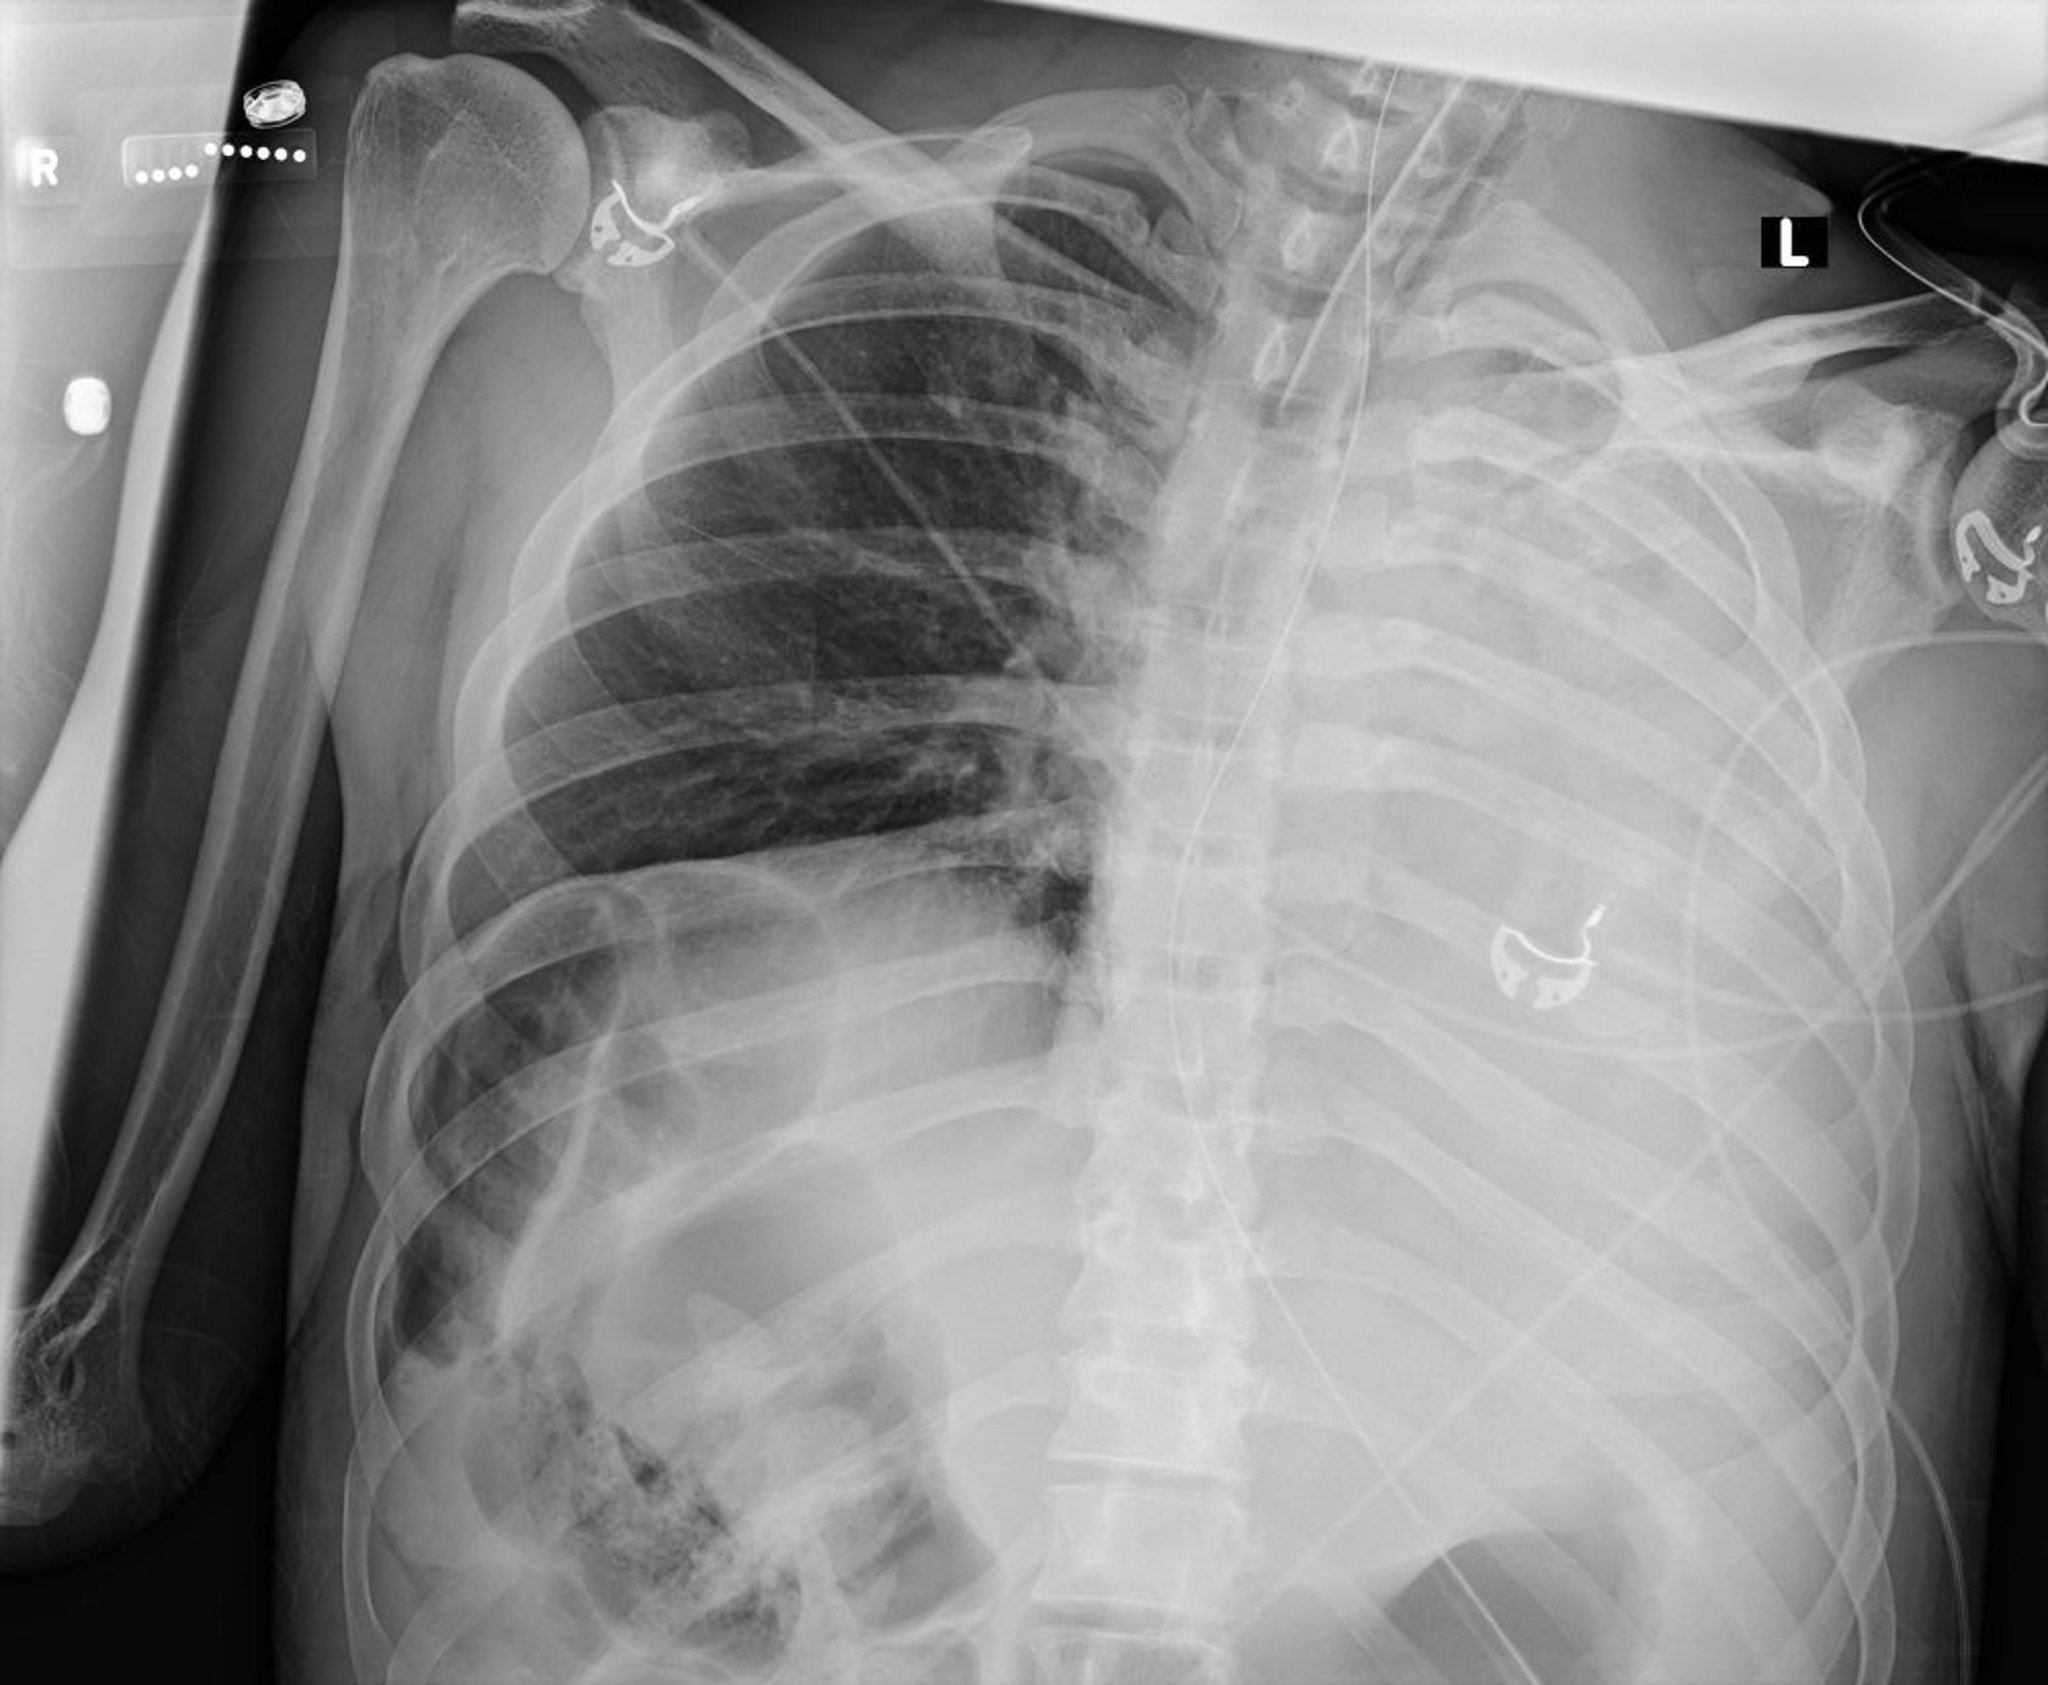

Dieses Thoraxröntgenbild zeigt einen Kollaps aller Lappen der linken Lunge infolge eines Schleimpfropfs.

Courtesy of Alexander S. Niven, MD